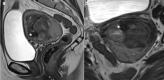

Although rare, uterine sarcoma is a diagnosis that no one wants to miss. Often benign leiomyomas (fibroids) and uterine sarcomas can be differentiated due to the typical low T2 signal intensity contents and well-defined appearances of benign leiomyomas compared to the suspicious appearances of sarcomas presenting as large uterine masses with irregular outlines and intermediate T2 signal intensity together with possible features of secondary spread. The problem is when these benign lesions are atypical causing suspicious imaging features. This article provides a review of the current literature on imaging features of atypical fibroids and uterine sarcomas with an aide-memoire BET1T2ER Check! to help identify key features more suggestive of a uterine sarcoma.